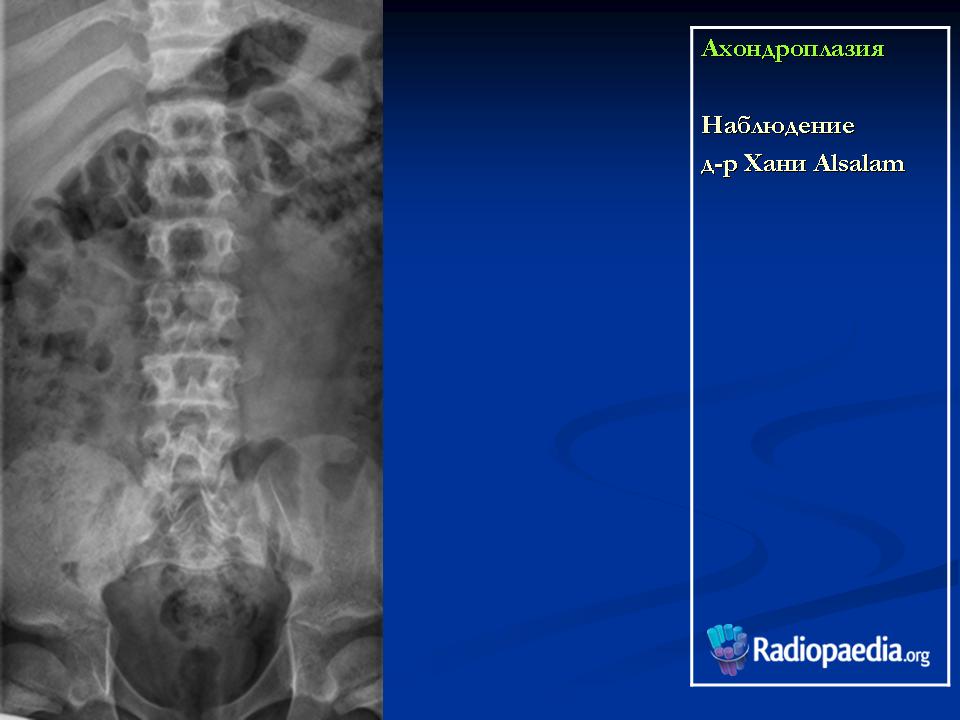

Ахондроплазия

http://radiopaedia.org/images/392220

http://radiopaedia.org/cases/achondroplasia

Ахондроплази́я (диафизарная аплазия, болезнь Парро-Мари, врожденная хондродистрофия) — известное с древности наследственное заболевание человека, проявляющееся в нарушении процессов энхондрального окостенения (вероятно, в результате дефектов окислительного фосфорилирования) на фоне нормальных эпостального и периостального окостенений, что ведет к карликовости за счет недоразвития длинных костей; характеризуется наличием врождённых аномалий, в частности врождённого стеноза позвоночного канала. Наследуется по аутосомно-доминантному типу.